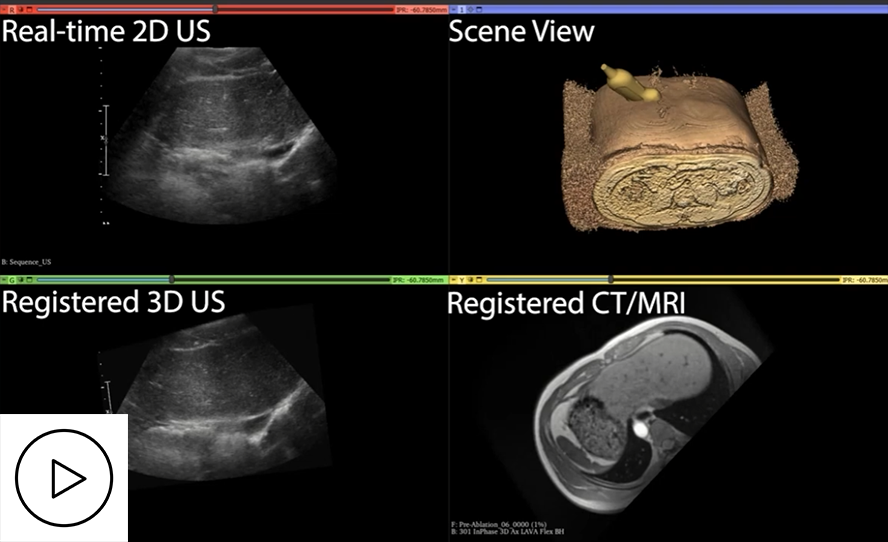

The 3DLIVUS system comprises a counterbalanced arm with encoders and electromechanical locks, a motor-driven 3D US scanner mounted at the arm end, and a workstation with customized control software (see Figure 1). It interfaces with any commercial US machine and uses joint encoders in the mechatronic arm for pose tracking, eliminating susceptibility to clinical environmental factors. Operating passively, it allows users to freely maneuver the US transducer while also supporting automated motion along predefined trajectories—60° tilting around the X-axis, 60 mm translation along the Z-axis, and rotation–translation hybrid.

Figure 2 illustrates the proposed framework for integrating 3D US into the standard clinical ablation workflow. This framework enhances the capabilities of 3D US imaging for improving percutaneous tumour ablation and demonstrates its potential to expand the therapeutic role of 3D US in clinical interventions. Specifically, the workflow is augmented with intra-procedural tumour coverage assessment (Project 2), tumour identification (Project 3), and multimodal visualization with instrument tracking (Project 4).

Figure 2. Framework for 3D US integration into conventional 2D US guidance. (a) 3DLIVUS system; (b) intra-procedural guidance. Note: the role of 3D US is highlighted in a brown block. (Regi: Registration, Recon: 3D US reconstruction)

The idea of our proposed method is to divide the direct 2D US-to-CT or MRI registration into two components, which are 3D US-to-CT or MRI registration and 2D US-to-3D US registration (see Figure 11). This decomposition strategy could significantly reduce the computational burden for registration algorithms. In addition, the introduction of 3D US images does not increase the clinical workload complexity. The 3D US image acquisition only requires 7s-12s for a single image, and this image can also improve intra-procedure tumour coverage, as demonstrated previously. For this project, we developed a series of registration methods, including rigid 3D US-to-CT/MRI registration, deformable 3D US-to-CT/MRI registration and rigid 2D-to-3D US registration (see Figure 12).

Figure 12. Detailed registration overview of 2D US-to-CT/MRI images